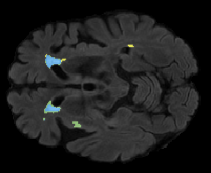

We evaluated our method in segmenting WMH from T1-w images using: a) Synthesized FLAIR images by treating the synthesis as a preprocessing step – we will refer to this method as offline synthesis; b) Synthesized FLAIR images using the proposed method, and c) without any synthesis – we will refer to this method as Unimodal. Baseline methods are illustrated in Figure 2

Table 2: Segmentation results for all proposed methods, each column represent a different slide in the image, blue areas are regions which were correctly labeled, false positives are shown in green, and false negatives in yellow

In order to better understand the above results, we visually analyzed the output segmentation performed for each method. Table 2 shows the results for three different slices (one slice per column). As illustrated, the proposed method is able to produce less false positives. It is also important to note that, unimodal segmentation is the one that produces more false positives, showing the advantage of using synthetic data. Regarding the nature of false positives, it can be easy to see in the third column a large number of false positives are on the border of periventricular lesions for the Unimodal method in comparison to the proposed method. Also from the first and second column, it can be observed that Unimodal tend to produce more small regions of false positives near to cortical areas. Removing such false positives requires additional post-processing steps, therefore, it is of value avoid this kind of over-segmentation. It can also be noted that synthesis methods tend to produce the same kind of false negatives, this may be due to the blurring effects in synthesized images since the information available during testing is limited – which otherwise is available from a FLAIR sequence.